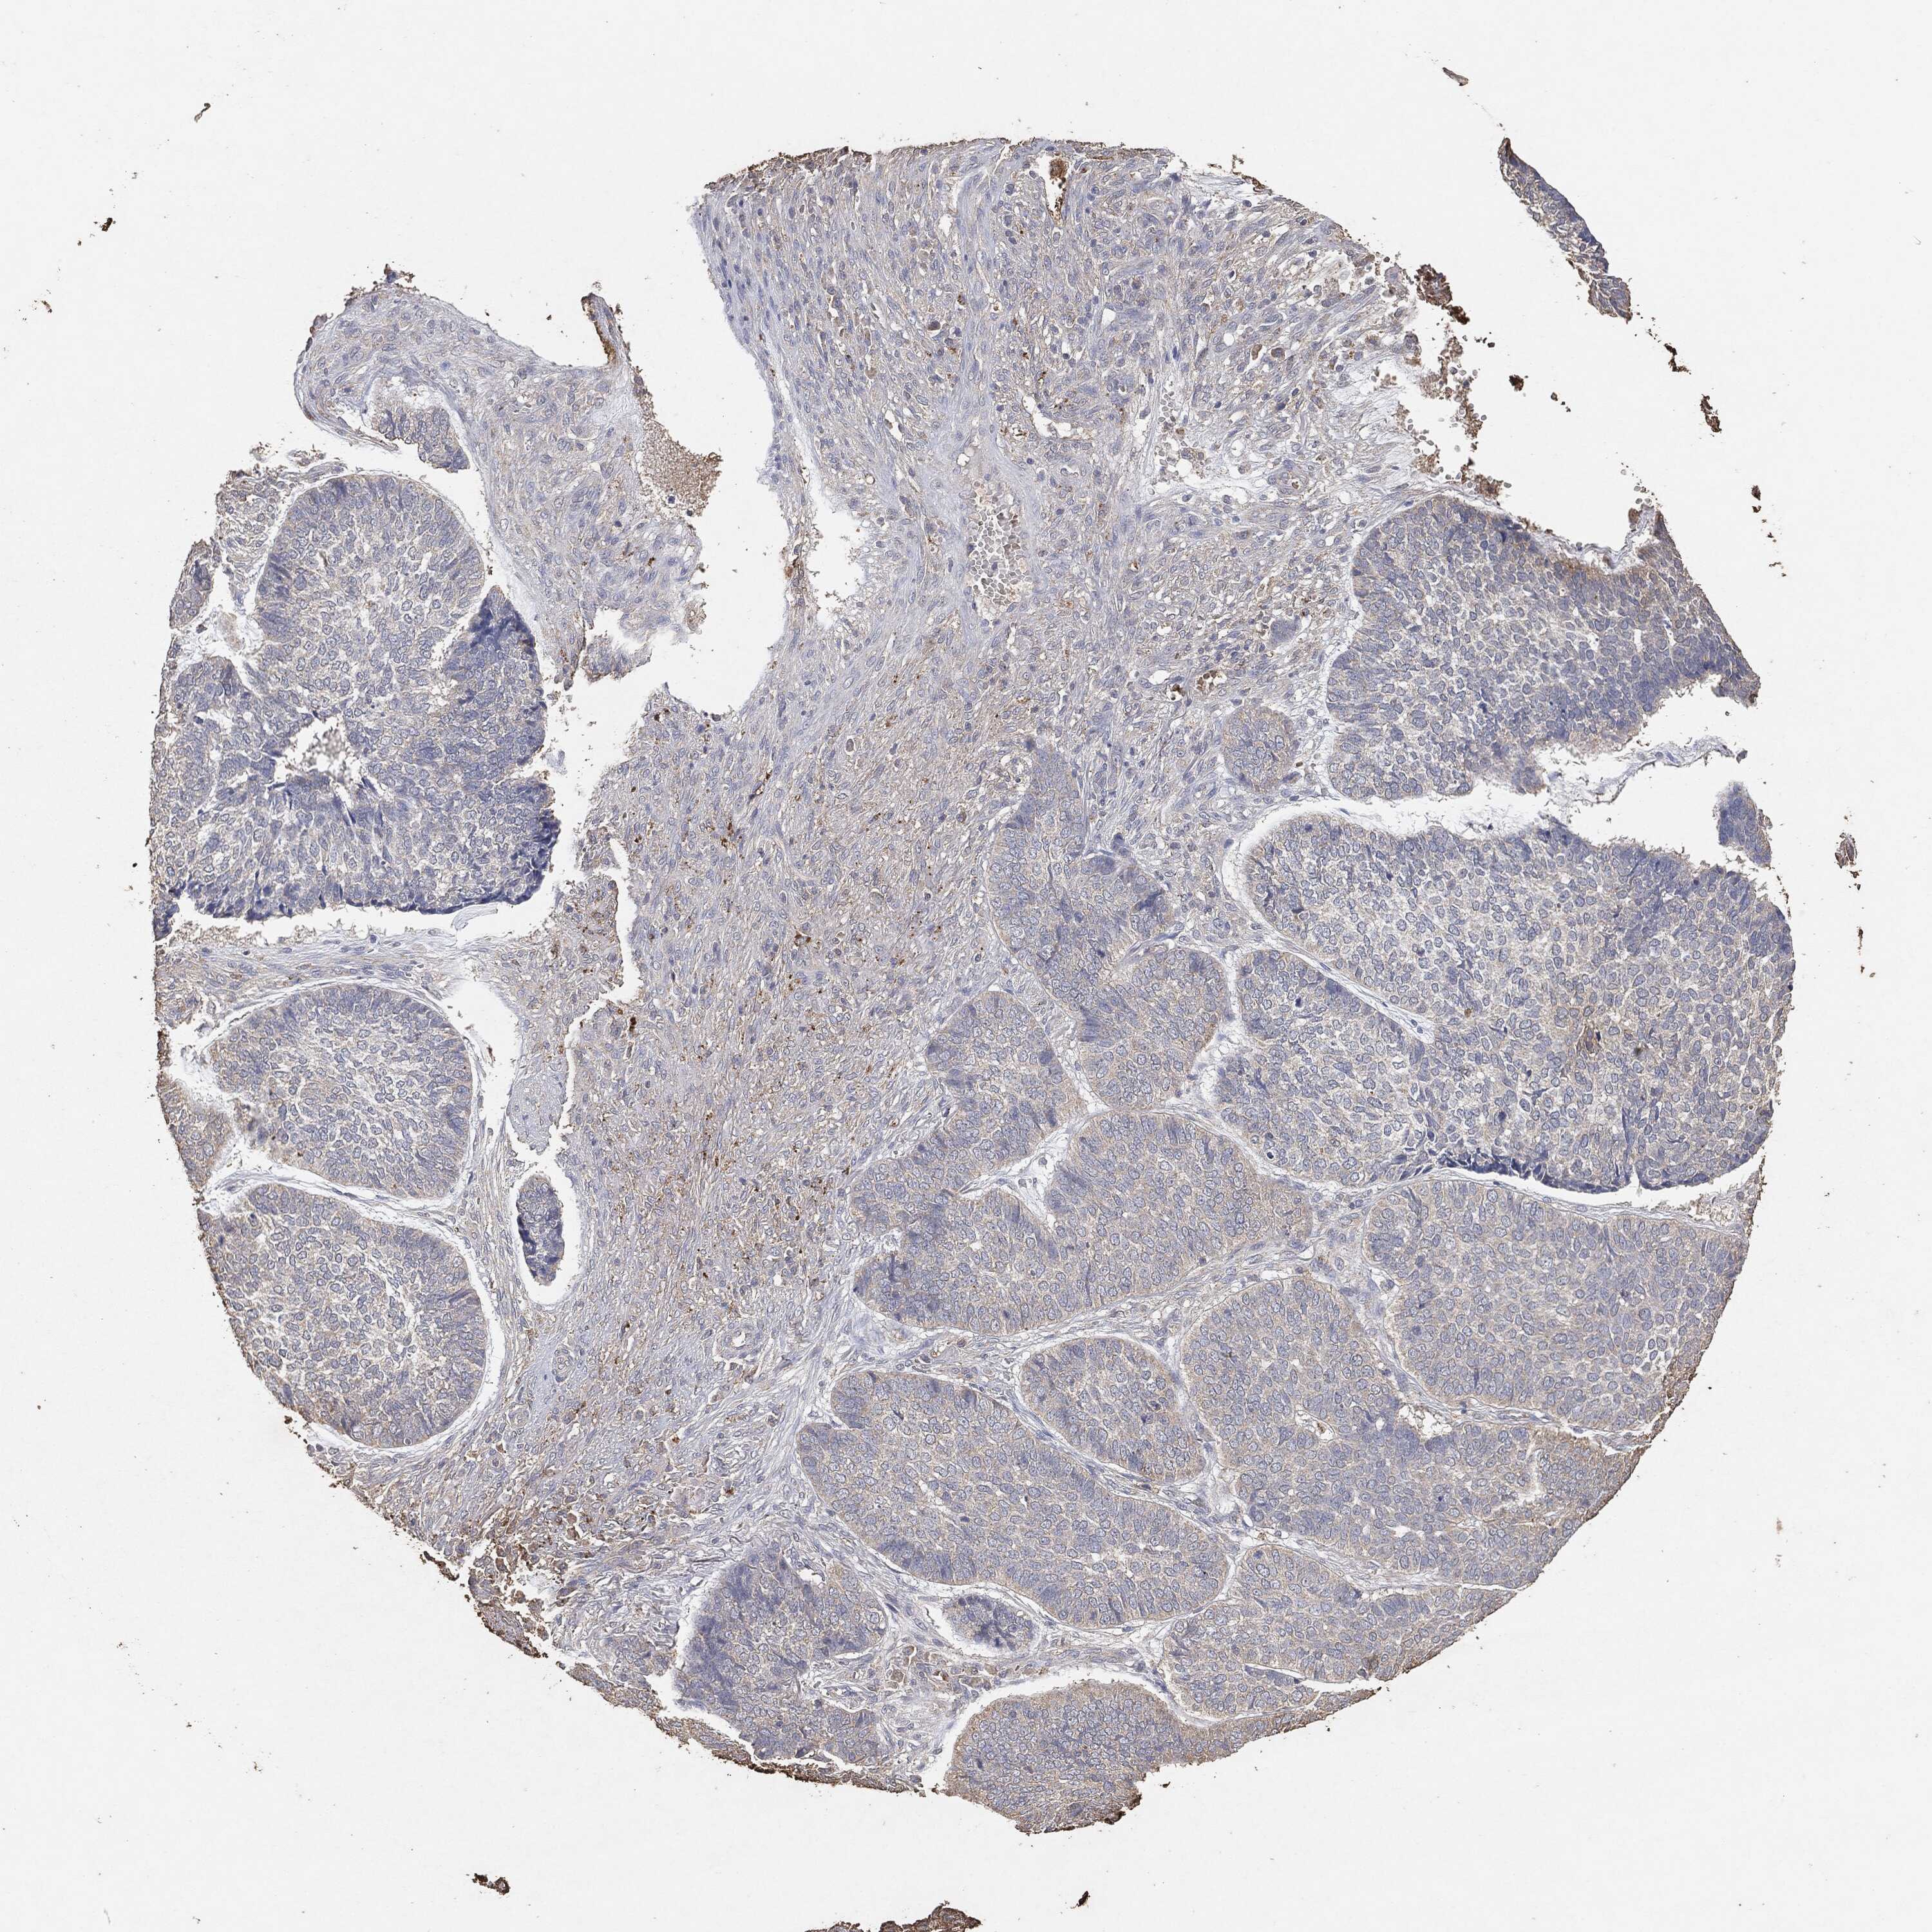

SKIN CANCER - Protein expressioni

A mouse-over function shows sample information and annotation data. Click on an image to view it in a full screen mode. Samples can be filtered based on level of antibody staining by selecting one or several of the following categories: high, medium, low and not detected. The assay and annotation is described here.

Each image is clickable and will lead to virtual microscopy that enables deeper exploration of all samples and also displays staining intensity scores, fraction scores and subcellular localization as well as patient and tissue information for each sample.

Staining

High

Medium

Low

Not detected

Intensity

Strong

Moderate

Weak

Negative

Quantity

>75%

75%-25%

<25%

None

Location

Nuclear

Cytoplasmic/membranous

Cytoplasmic/membranous,nuclear

Squamous cell carcinoma, NOS

Squamous cell carcinoma, metastatic, NOS